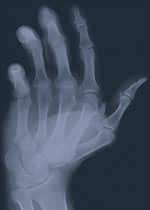

Bone mineral density (BMD) assessment seeks to determine whether a person has osteoporosis or osteopenia (low bone mass associated with increased risk for osteoporosis).

The World Health Organization defines osteopenia as a condition in which a woman’s BMD is at least one standard deviation, but not more than 2.5 standard deviations, below the average BMD of a healthy young woman at peak bone density. This correlates with a BMD T-score of -1 to -2.5. Women who have a BMD of more than 2.5 standard deviations below the young adult reference range, or a BMD T-score of less than -2.5, are considered to have osteoporosis. As a general rule, a woman’s risk of fracture doubles for every standard deviation below the young adult reference range. For example, if a patient’s T-score is -2, she has a four times greater risk of suffering a fracture than a young woman at peak bone density.

While BMD testing is useful for assessing the mineral content of bones, it does not assess the quality of the connective tissue matrix supporting those minerals. Specialists now think that the quality of a bone’s collagen-based matrix structure is even more critical in preventing fractures than is the degree of mineralization. Unfortunately, there is no widely available test to directly and non-invasively measure the health of a person’s ground substance. While the BMD test does not provide a complete picture of bone health, it remains the test best able to help gauge a person’s risk of fracture. BMD test results can be used in concert with specific markers for bone turnover in the serum and urine to develop a more complete assessment of osteoporosis risk.